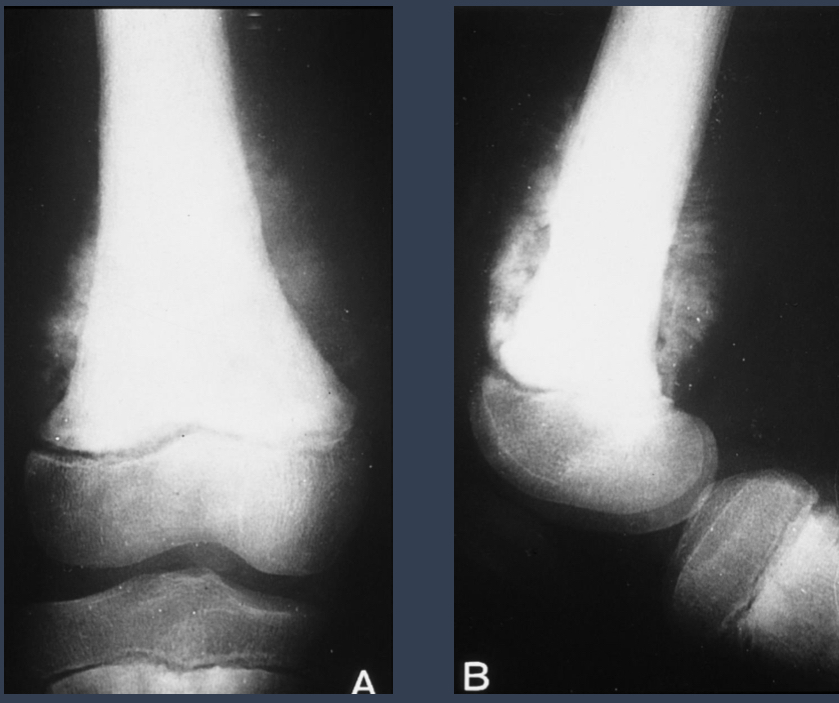

what is this?

ABC

describe this. what is this?

distal radius

extends into subchondral region

diminished bone density

appears aggressive

malignant GCT